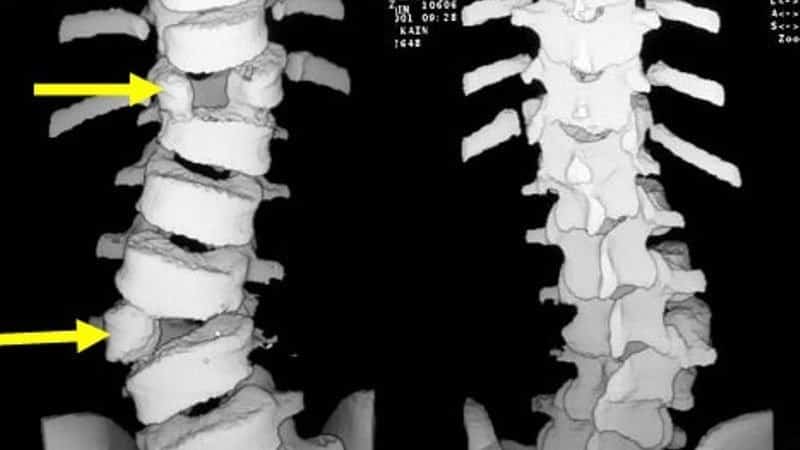

Выявить аномалии развития позвоночного столба может ортопед или хирург. При осмотре пациента врач отмечает искривления, нарушения осанки, вплоть до формирования горба. На рентгенографии во фронтальной плоскости две половинки позвонка суживаются без слияния по направлению к центру, образуя фигуру, напоминающую крылья бабочки.

Компьютерная и магнитно-резонансная томографии позволяют оценить состояние межпозвонковых дисков, нервных стволов, сосудов, спинного мозга. Эти методы используются для уточнения диагноза уже после того, как проведен хирургический и неврологический осмотр пациента.

При бабочковидном позвонке проводят следующие виды операций:

- спондилодез — операция по фиксации смежных позвонков;

- спондилодез с внедрением металлоимплантов;

- полное удаление патологического позвонка и коррекция деформации.